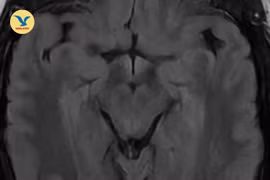

Nhìn mờ chỉ định chữa mộng mắt không khỏi, hóa ra huyết khối tĩnh mạch não

Bệnh không có triệu chứng điển hình, thường tiến triển âm thầm và bộc phát bất ngờ. Nếu thấy những biểu hiện như mờ mắt, buồn nôn, đau đầu... cần đi khám ngay.